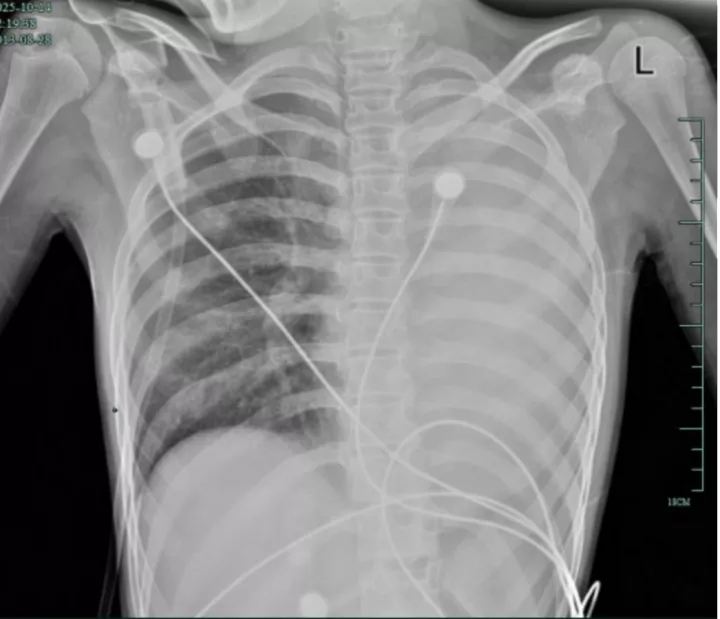

治疗前,左肺呈“白肺”状态

入院后,她很快出现呼吸急促、胸闷胸痛,只能靠5L/min的面罩吸氧维持血氧,胸片显示左肺已完全呈 “白肺”

改变,肺部炎症进展迅猛。